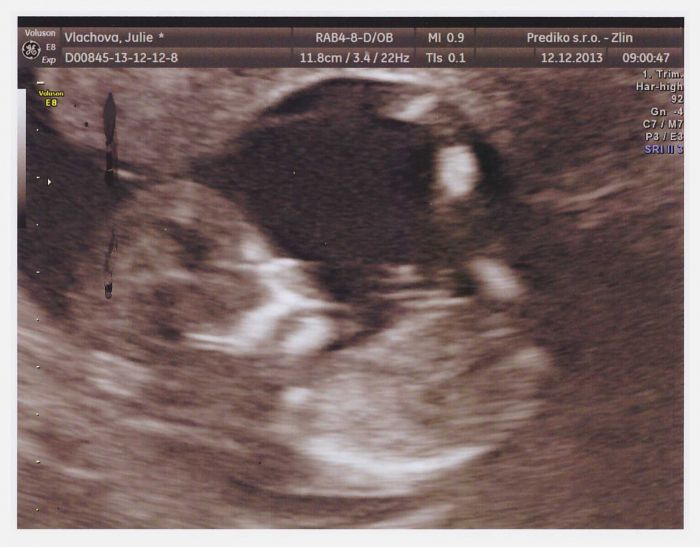

Autor: Julie 23 12.12.2013 v 15:16

Děvčátka, musím se Vám pochlubit, dnes jsem byla na screeningu a jsme oba dva v naprostém pořádku!!! Miminko si pěkně spokojeně vegetí v bříšku s nožičkou nahoře !!!

ptala jsem se na pohlaví, ale ještě to nejde pořádně rozpoznat, takže se necháme s přítelem překvapit až do února, kdy jdu na 2.screening...:)) Všem maminkám a miminkám přeji hodně zdaru a ZDRAVÍČKA !!